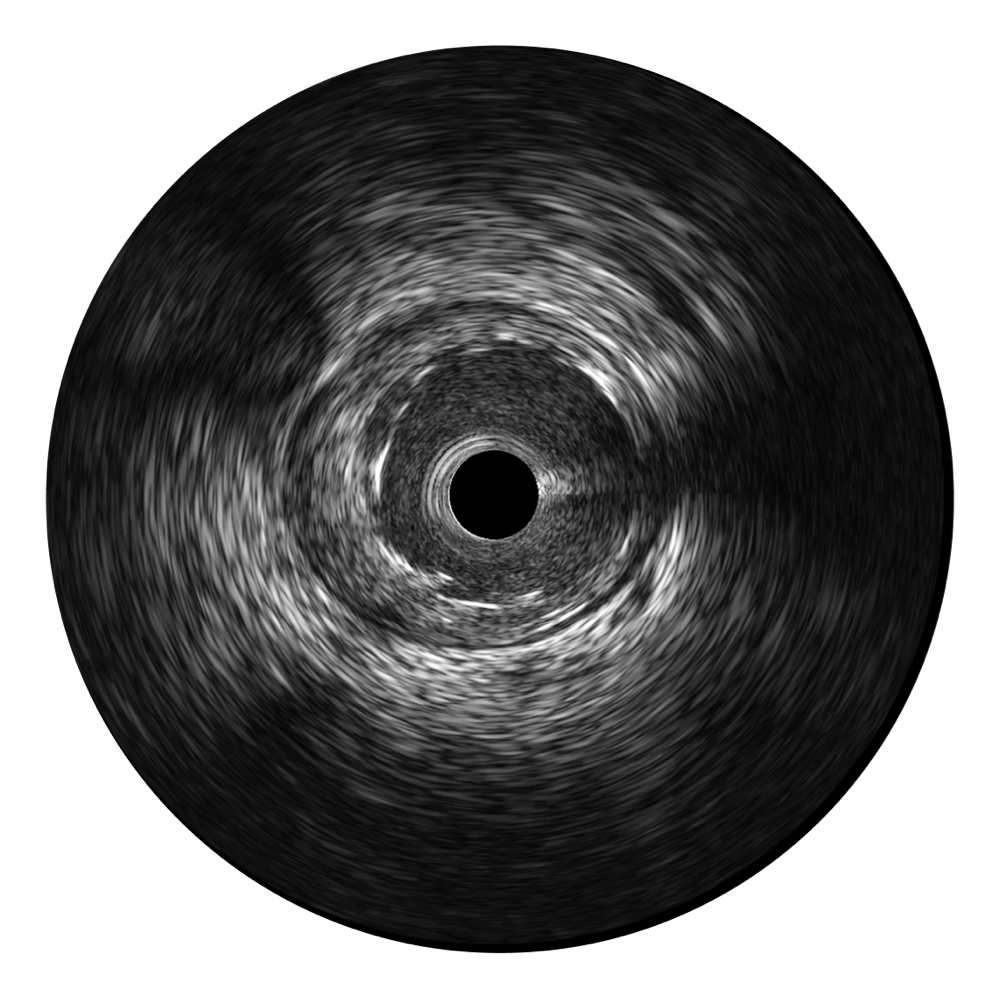

传统IVUS图像

对比传统IVUS导管成像,九州酷游宽频IVUS图像的近场支架梁显影更细腻,远场中膜外血管仍清晰可辨,兼顾远中近,兼顾分辨力与穿透深度